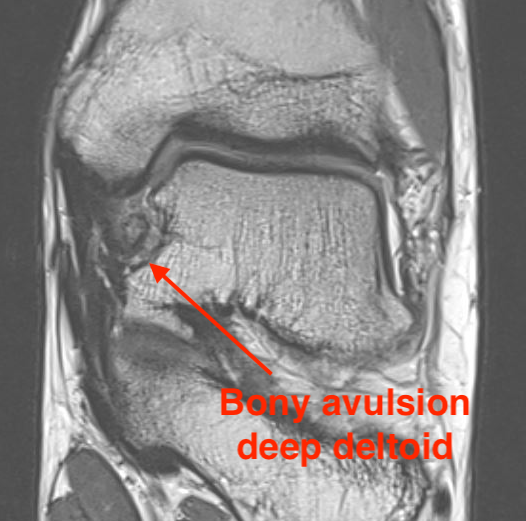

MRI

Old bony avulsion of deltoid ligament